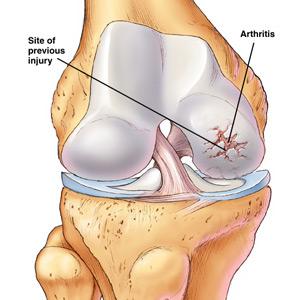

3.關節病變與變形性骨炎相伴的關節病變有關節畸形、退行性關節病變、軟骨鈣鹽沉積和假性痛風、鈣化性關節周圍炎等。骨病變畸形可能導致關節畸形,但變形性骨炎本身很少侵犯關節軟骨面;當骨畸形累及髖關節相鄰部位時,因運動應力異常可導致關節異常磨損軟骨缺損,而下層出現假血管瘤樣物晚期出現髖臼內陷。膝關節也有類似情況。在遠離病灶的部位,可出現鈣化與病變的擴展無關。

為雙顳部顱骨增大,前額隆起,頭皮靜脈曲張,一側或雙側神經性耳聾或耳硬化症,眼底有血管樣紋,軀幹矮而駝背,形似猿猴。蹣跚步態,股或小腿前外側彎且有骨膜壓痛和溫度升高。聽覺喪失,脊髓狹窄症,不全麻痹或截癱均為神經受壓的表現。因Paget骨病是代謝活躍而且血管嚴重受累的病變,故可發生高排性心力衰竭。彎曲的長骨與鄰近關節的骨關節炎可發展為畸形。可發生病理性骨折。約1%的病人發生肉瘤變性,此時疼痛越來越劇烈。